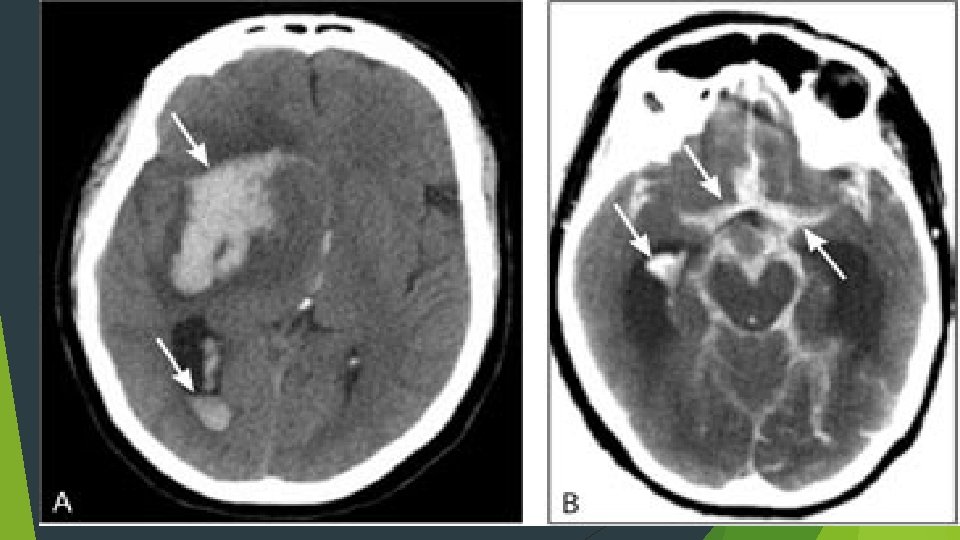

IMAGING CT…reliable for intracranial hemorrhage close to 100% sensitive not sensitive for ischemic CVA…especially early MRI…diffusion weighted hyperdense regions of ischemia can detect ischemia after 5 -10 minutes time consuming…. cooperation issues ECHO…echocardiography can identify source of cerebral emboli identify patent foramen ovale

rt. PA {Alteplase} With normal or early ischemic change on imaging If frank hypodensity >1/3 MCA no rt. PA Unclear use…mild deficits improving CVA symptoms surgery< 3 months recent MI Maybe harmful in pts on dabigatran, apixaban, rivaroxiban Other lytics…not recommended (streptokinase) or investigational

Treatment of Complications Brain edema/Increased ICP…peaks 3 -4 days after CVA restriction free water avoid excess glucose minimize hypoxemia and hypercarbia treat hyperthermia elevate HOB 20 -30 degrees avoid antihypertensive agents causing cerebral vasodilation Treatment of increased ICP hyperventilation, hypertonic saline, osmotic diuretics Interventricular CSF drainage Steroids not recommended decompressive surgery…effective…decisions based on volume of tissue infarcted and midline shift